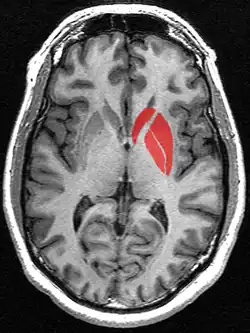

![]() | ||||

De basale kernen, waar het putamen toe behoort, aangegeven in het paars. | ||||